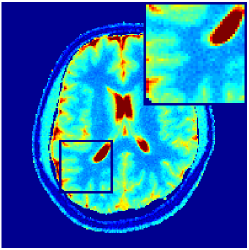

Two sets of experiments were conducted here: first, we used the 2D and 3D acquisition sequences for scanning a healthy volunteer’s brain (real-world acquisitions). Figures 6 and 7 display the parametric maps reconstructed from 2D spiral and radial readouts. We computed the T1, T2 and proton density (PD) maps using baseline reconstruction algorithms ZF, VS, LR, FLOR, AIR-MRF and our proposed LRTV. While baselines use DM either for quantitative inference or also during reconstruction (i.e. AIR-MRF), we further compare the DM-free LRTV’s performance when cascaded to DM, KM and MRFResnet for quantitative inference. For the 3D spiral acquisitions we compared LRTV and its closest competitor VS in Figure 8. Outcomes from other tested algorithm are displayed in the supplementary materials (Figure S5). Since FLOR does not use dimensionality-reduction, our system ran out of memory during 3D reconstruction; hence results are not reported in this case.

VI-E1 Discussion

The LRTV-DM and LRTV-MRFResnet perform on par, and both outperform all tested baselines for reconstructing T1, T2 and PD maps in all acquisition schemes. This can be observed both visually in Figures 6, 7, 8, S2 and S3, and quantitatively in Table IV across all tested metrics. Other baselines were unable to successfully remove the under-sampling artefacts in TSMIs, and these errors propagated to the parameter inference phase and resulted in inaccurate maps. Temporal-only priors incorporated within LR are shown insufficient to regularise the inverse problem and LR sometimes (e.g. 2D spiral acquisitions) can admit solutions with even stronger artefacts than the model-free ZF baseline. This issue was previously studied for other non-Cartesian MRF readouts that similar to our spiral/radial trajectories, miss to sample the corners of the k-space in all timeframes (see section 2.2.2 and figure 2 in [19]). In the absence of reference for the k-space corners information, the LR iterations despite minimising the objective can converge to solutions with high-frequency artefacts, as visible in the computed maps. This highlights the need for adding an appropriate spatial-domain regularisation. FLOR reduces the LR’s artefacts but this improvement is limited because the suggested nuclear norm penalty does not incorporate an explicit spatial regularisation. Further for reducing artefacts, FLOR can introduce an undesirable bias in the computed T1/T2 maps e.g. see error maps in Figures S2 and S3. The non model-based VS baseline incorporates spatial regularisation and results in spatially smoother maps than ZF and LR, but it is unable to output artefact-free images. Further and consistent with our in-vitro experiment, we observe that VS overestimates the T2 values (e.g. in White and Grey matter regions) in tested 2D acquisitions i.e. the spatial regularisation trades off agains the quantification accuracy. The model-based AIR-MRF adds spatial regularisation through 2D/3D low-pass Gaussian filters however this trades off the sharpness of the computed maps and can increase the errors at the tissue boundaries (we searched Gaussian spreads that keep the blurs and high-frequency artefacts minimal). For our acquisition readouts, Gaussian filters performed better than disk filters of [19] for avoiding strong Gibbs artefacts. On the other hand, the spatiotemporally regularised LRTV greatly improves the TSMI reconstructions i.e. 4 dB enhancement compared to the closest competitor baseline (Table IV). This enables computing accurate and aliased-free multi-parametric inference using DM or the DM-free learning-based alternative MRFResnet as visible in Figures 6, 7, 8, S2 and S3. MRResnet and DM score competitive quantitative inference results i.e. T1 and T2 MAPE less than 5% and 9%, respectively (Table IV). KM also outputs comparably accurate T1 maps, however this shallow learning model despite having a model size larger than MRFResnet, is unable to learn accurate T2/PD quantification and it results in poor estimated maps, consistent with our observations in section VI-C.